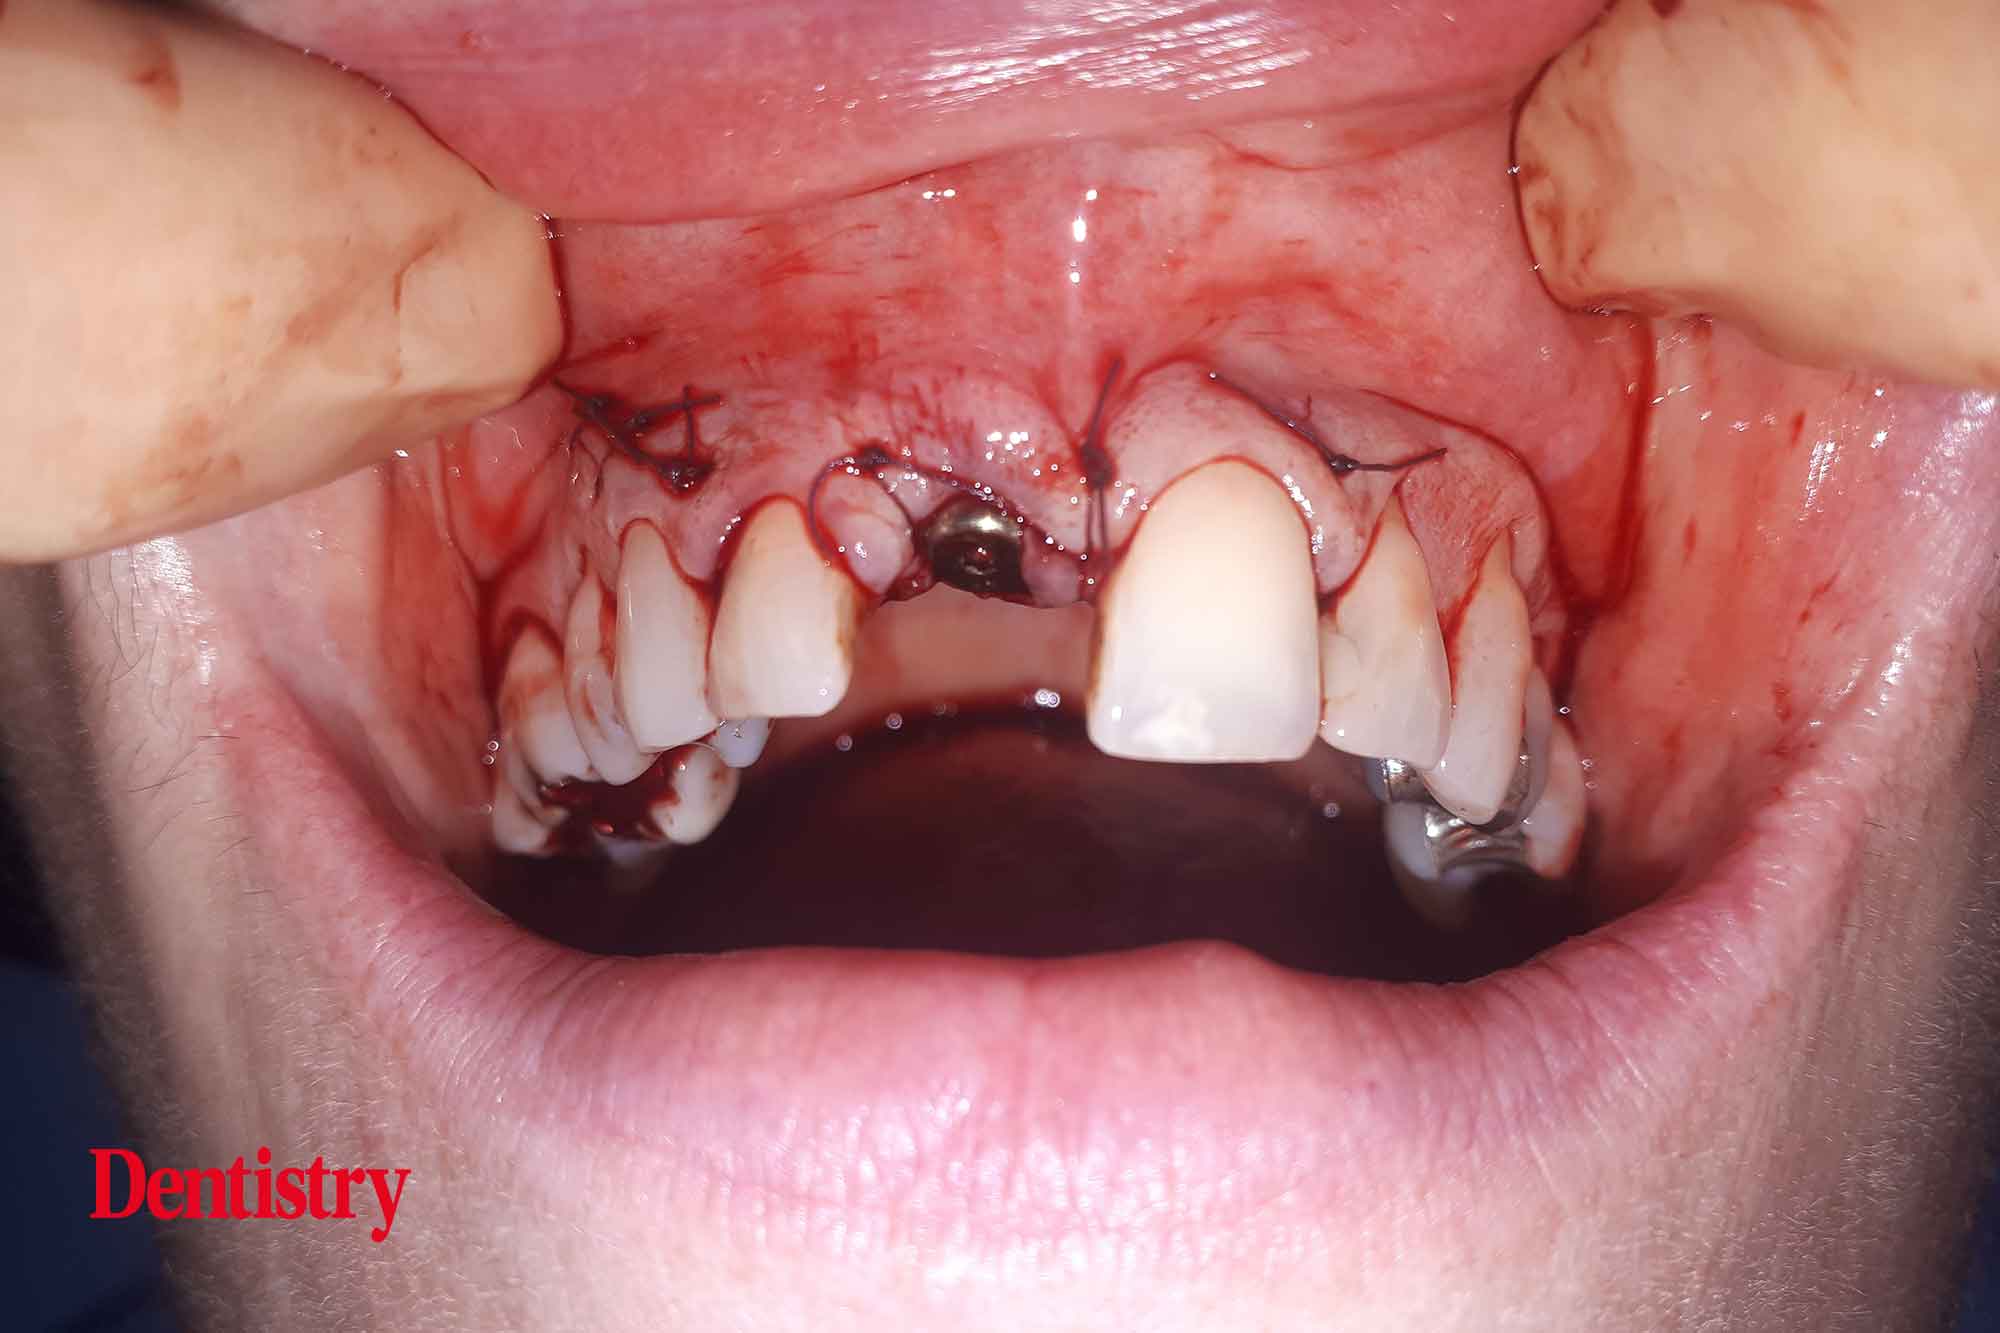

Local anaesthetic was delivered using articaine. Once the patient had confirmed the anaesthetic was working, a three-sided flap was raised. Buccal bone grafting was required and visualisation is key.

The root was then carefully removed, ensuring the buccal plate was left intact. The guide was then checked in place to confirm a passive fit.

Next, an osteotomy was prepared to the predetermined length, ensuring no lateral movements. The guide had been designed to engage both palatally and apically to the root socket.

Next, the implant was inserted to 45Ncm torque, again confirming good primary stability and insertion torque. This is key had the patient wished to have the tooth immediately restored with a temporary crown.

A periosteal-relieving incision was performed pre-grafting to allow for tension-free closure.

Approaching the end of the appointment, autogenous bone chips were collected and applied to the implant surface. As well as application of a layer of xenograft with a resorbable membrane.

The resorbable membrane was held in place by the healing cap and tension-free closure was performed using resorbable sutures.